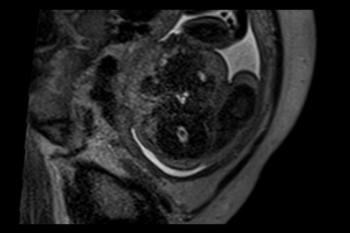

Figure 5. Images obtained in the case of a 33-year-old woman who had a rash at 10 weeks of pregnancy, with confirmed Zika virus infection. US performed at 19 weeks of gestational age showed a head circumference in the normal range (16.6 cm). (a, b) Sagittal and (c) coronal transvaginal US images obtained at the next US examination at 27 weeks 2 days of gestational age, however, showed the fetal head circumference to be 21.6 cm, which corresponded to 23 weeks 3 days (˂2.3 percentile, not shown). There was mild ven¬triculomegaly with septations in the occipital horns. Calcifications could be seen at the gray matter–white matter junction. The cerebrum was atrophic. There was blood clot in the region of the confluence of sinuses (arrow on c). (d) Coronal, (e) axial, and (f) sagittal T2- weighted fetal MR images obtained at 32 weeks show septations in the ventricles and an abnormal-appearing cortex, with a thickened and undersulcated cortex most marked on the left, compatible with polymicrogyria. The sagittal midline view shows microcephaly, blood clot in the region of the confluence of sinuses, and prominent skin folds. (g, h) Axial T2-weighted and (i) sagittal T1-weighted postnatal MR images obtained in the 4-week-old neonate show diffuse gyral abnormality and abnormal myelination. The septations in the ventri¬cles are again seen. The sagittal image shows thinning of the spinal cord at the craniocervical junction.

High-res (TIF) version